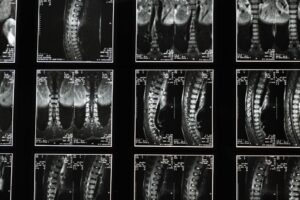

좌골신경통 혹시 나도, 내 몸에 나타나는 증상들 핵심정리

좌골신경통의 다양한 증상을 쉽고 명확하게 정리했습니다. 혹시 나도? 하는 생각이 든다면, 내 몸의 신호를 파악하고 핵심 정보를 확인하세요.